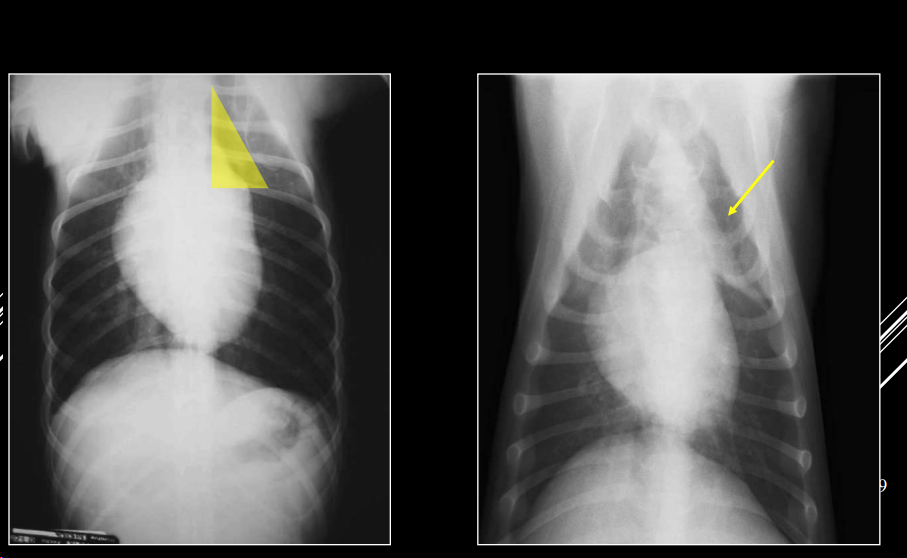

3. Alteraciones de anchura del mediastino craneal

- En perros: anchura < 2x VT.

- En gatos: anchura ≈ VT.

- En braquicéfalos/obesos puede verse mayor (grasa mediastínica).

- Generalmente en gatos es por un linfoma.

Causas:

- Derrame mediastínico.

- Masas mediastínicas (craneodorsales, hilares, caudodorsales, caudoventrales, craneoventrales).

- Linfomas en gato, timomas en perros.